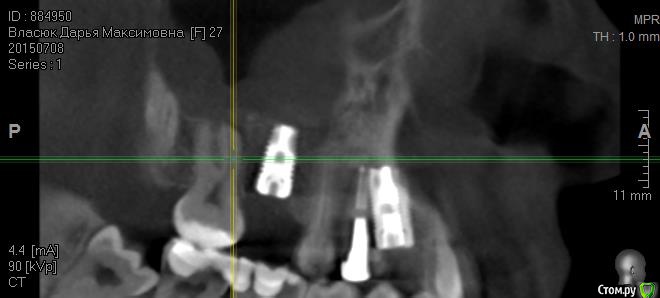

fifa888.dexo Опубликовано 22 июля, 2015 Автор Поделиться Опубликовано 22 июля, 2015 а это все что я могла придумать с кт Ссылка на комментарий

diesel87 Опубликовано 22 июля, 2015 Поделиться Опубликовано 22 июля, 2015 http://fs2.directupload.net/images/150723/9sv48h7l.jpg http://fs1.directupload.net/images/150723/9nsd29hm.jpg http://fs2.directupload.net/images/150723/q4s456ou.jpg http://fs2.directupload.net/images/150723/9x7h27mc.jpg По КТ:1.возможно имплант в области клыка в апексе (самой верхней части) контактирует с четверкой (не ясно из-за того что имплант фонит), если четверка не реагирует, то пока наблюдать, делать прицельные снимки раз в 3/6/9/12 месяцев.2. Не докрученный формирователь, особо не страшно, но в щель может врасти десна, будет запах, локальное воспаление в области шейки импланта, так что лучше его докрутить или если он упирается в соседние зубы, поменять на узкий и докрутить.3. Имплант что в синусе, по снимку он практически весь в кости, а "воспаление" могло быть там и ранее, есть снимки до операции?? Ссылка на комментарий